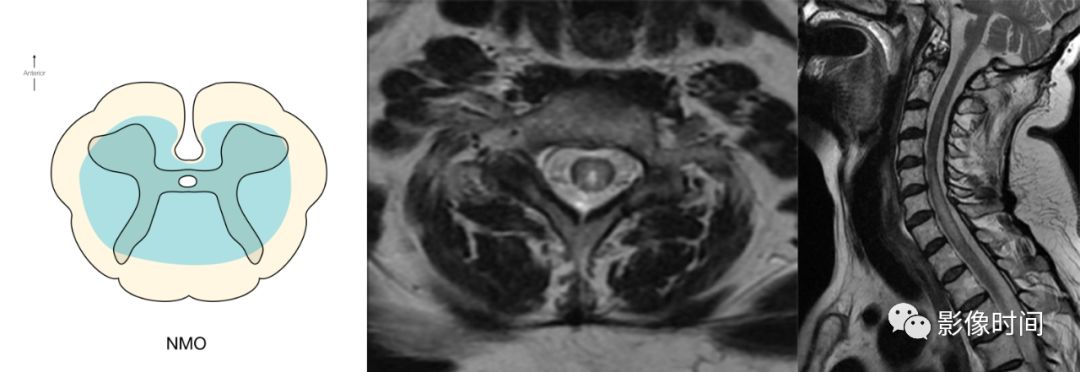

神经脊髓炎谱系疾病(neuromyelitis optica spectrum disorder,NMOSD):是一种由水通道蛋白-4(AQP-4)自身抗体介导的炎性脱髓鞘疾病,青年或中年女性较多见,临床常为双侧视神经炎和脊髓炎导致失明和截瘫,也可累及大脑。

MRI:

脊髓:病灶 T2WI 呈高信号,T1WI 呈稍低信号,急性期出现斑片状或云雾状强化,轴位常位于脊髓中央,长度>3 个椎体长度。亮点征:轴位 T2WI 很高信号的多发斑点,信号高于脑脊液,特异性=97%。

病灶分布于脊髓中央,长度大于3个椎体,亮点征